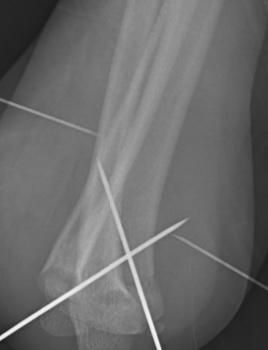

Cada caso es valorado a profundidad para proponer tratamientos conservadores (rehabilitación, ejercicios, ortesis) o procedimientos quirúrgicos cuando son necesarios, como artroplastías (colocación de prótesis articulares) o cirugías mínimamente invasivas como la artroscopía.